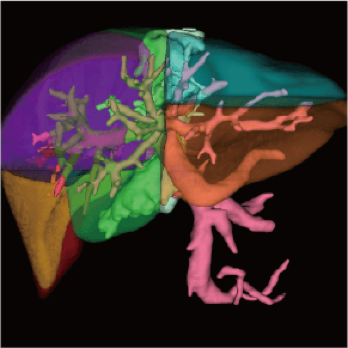

3 core components built on a new industry-leading configuration

Large-capacity tube delivers exceptional stability and durability, ensuring consistently high-quality output even under heavy workloads

High-power generator delivers high mA output for rapid scanning of complex anatomy and large coverage areas, boosting scan speed while enhancing image signal-to-noise ratio and minimizing artifacts

Wide detector expands single-rotation coverage, shortens exam time, reduces motion artifacts, decreases radiation dose, and saves tube exposure time while effectively lowering operating costs